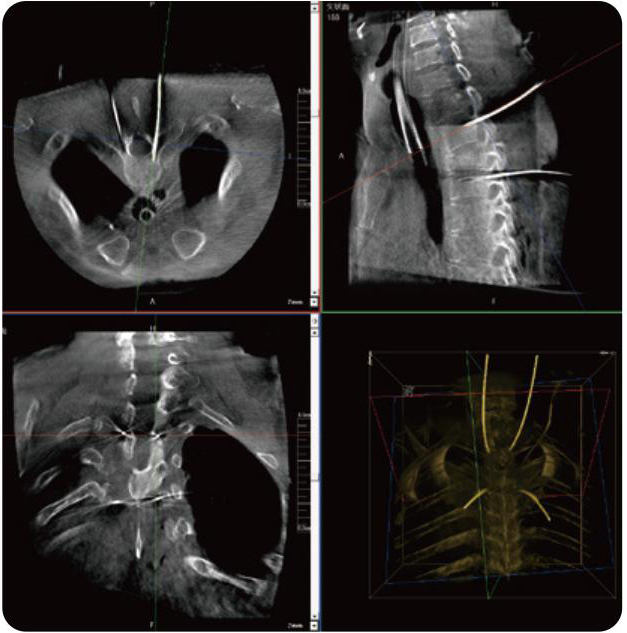

PL300B搭配普愛醫(yī)療自主研發(fā)生產(chǎn)的平板3D C形臂,借助一體化自適應配準( 軌跡配準)技術,通過追蹤C形臂三維采集軌跡,自動完成圖像坐標建立和系統(tǒng)坐標配準。配準精度更高,操作步驟少,系統(tǒng)運作效率高。